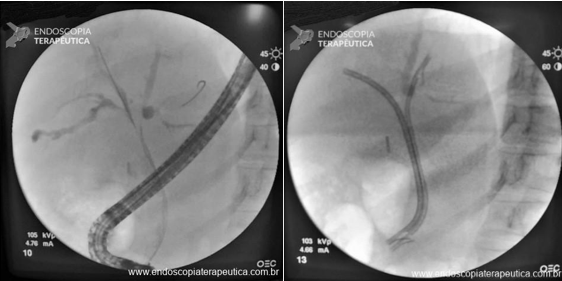

Nos pacientes ictéricos a CPRE também pode ser útil tratando as estenoses com a colocação de próteses biliares e identificando os padrões suspeitos da colangiopatia.

Tratamento das estenoses e paliação da icterícia por CPRE com passagem de prótese biliares.

Fonte da imagem: Mendoça EQ. Colangite por IgG4 como diagnóstico diferencial do colangiocarcinoma hilar. Endoscopia Terapeutica 2023, Vol 1. Disponível em: https://endoscopiaterapeutica.net/pt/colangite-por-igg4-como-diagnostico-diferencial-do-colangiocarcinoma-hilar/